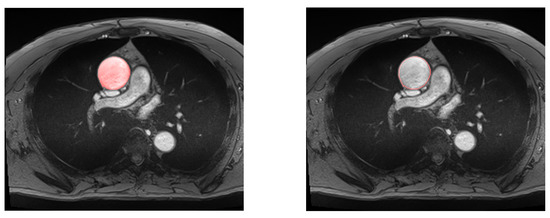

Figure 7.

Example of automatic segmentation of the ascending aorta with our U-Net architecture. On the left, all the aortic surface is colored, in contrast to the right, where only the aortic wall is displayed.

Considering that residual U-Net and simple U-Net had the highest performance, the simple U-Net was selected for the next phases as it has less complex architecture and provides a lower Hausdorff distance.